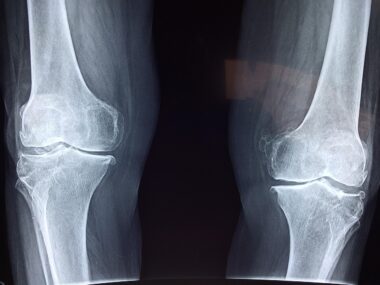

Anterior cruciate ligament (ACL) tears are prevalent among athletes participating in various sports, especially those involving rapid pivots, jumps, or sudden stops. Typically, these injuries are the result of trauma during athletic activities. Recognizing ACL tears early is crucial for effective management, as failure to do so may lead to further complications such as joint instability and chronic pain. Diagnosis often starts with a thorough medical history and a physical examination, focusing on the mechanism of injury. Medical professionals may utilize specific tests, like the Lachman test or the pivot shift test, to evaluate the integrity of the ACL. In some cases, imaging tests like MRI scans are essential for confirming the diagnosis. An accurate diagnosis allows for tailored treatment plans that consider the athlete’s age, activity level, and overall health. Thus, understanding the specific nature of an ACL tear is paramount for minimizing the risk of re-injury and ensuring a quick return to the field or court with optimal knee functionality.

ACL tears can be classified into three grades, indicating the severity of the injury. A grade I tear involves a slight stretching of the ligament; grade II involves a partial tear; and grade III signifies a complete tear. Symptoms can vary depending on the severity, but common indicators include significant swelling, intense pain, and a feeling of instability in the knee. Some individuals may also report a “popping” sound at the moment of injury, followed by swelling within a few hours. Treating an ACL tear depends on several factors, like the patient’s activity level, age, and injury severity. Conservative treatment options such as rest, ice, compression, and elevation (RICE) may suffice for low-demand athletes. Alternatively, active athletes might require surgical intervention, particularly in grade II and grade III tears. Surgery often involves reconstructing the torn ligament using a graft, either from the patient’s hamstring or from a deceased donor. This procedure aims to restore stability in the knee, allowing athletes to return to their activities efficiently.